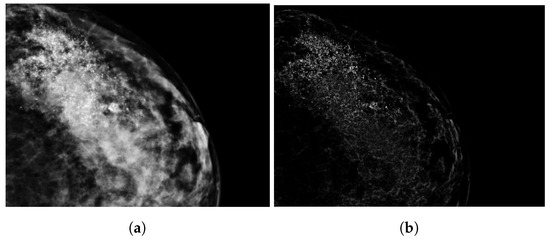

2.3. Tumor Segmentation

2.4. Radiomics Features